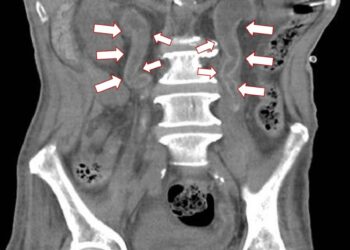

首頁 標籤 記者蕭麗鳳/彰化報導 61歲梁姓男子半年內因為泌尿道感染住院多達6次,日前再度發燒及泌尿道感染,轉院到衛福部彰化醫院就醫,多科會診發現,包括腎臟及輸尿管等泌尿道系統被一層像是水泥、蛋殼的鈣化物覆蓋,被稱為Encrusted

標籤: 記者蕭麗鳳/彰化報導 61歲梁姓男子半年內因為泌尿道感染住院多達6次,日前再度發燒及泌尿道感染,轉院到衛福部彰化醫院就醫,多科會診發現,包括腎臟及輸尿管等泌尿道系統被一層像是水泥、蛋殼的鈣化物覆蓋,被稱為Encrusted

影音/結石不成塊滿覆蓋泌尿道 醫師:多喝水 不要憋尿 適度運動

記者蕭麗鳳/彰化報導 61歲梁姓男子半年 ...